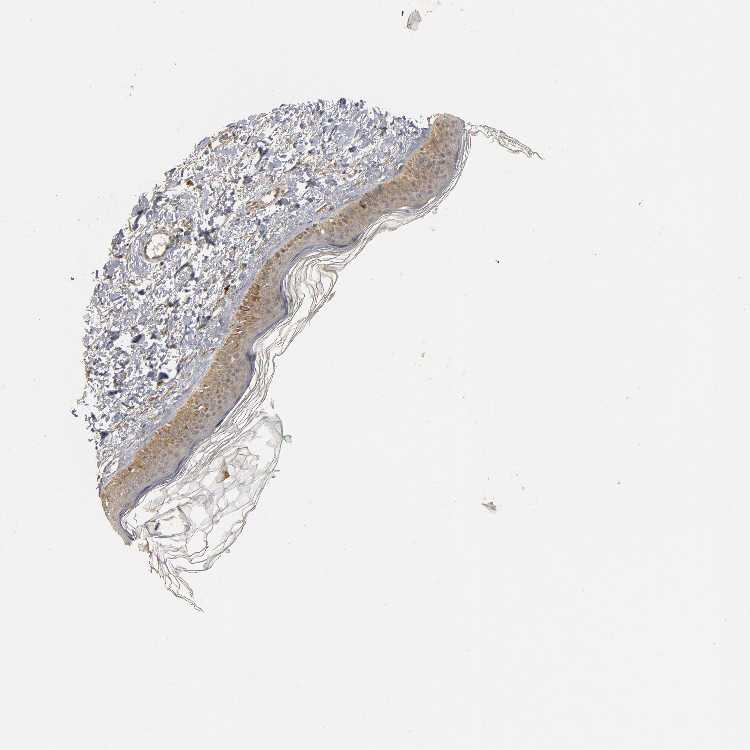

SKIN 1 - Antibody stainingi

Antibody staining in the annotated cell types in the current human tissue is reported as not detected, low, medium, or high, based on conventional immunohistochemistry profiling in selected tissues. This score is based on the combination of the staining intensity and fraction of stained cells.

Each image is clickable and will lead to virtual microscopy that enables deeper exploration of all samples and also displays staining intensity scores, fraction scores and subcellular localization as well as patient and tissue information for each sample.

Antibody HPA019805Antibody HPA020599Antibody CAB004605

Langerhans MediumNot detectedNot detected

Fibroblasts Not detectedLowMedium

Keratinocytes MediumMediumMedium

Melanocytes LowMediumMedium